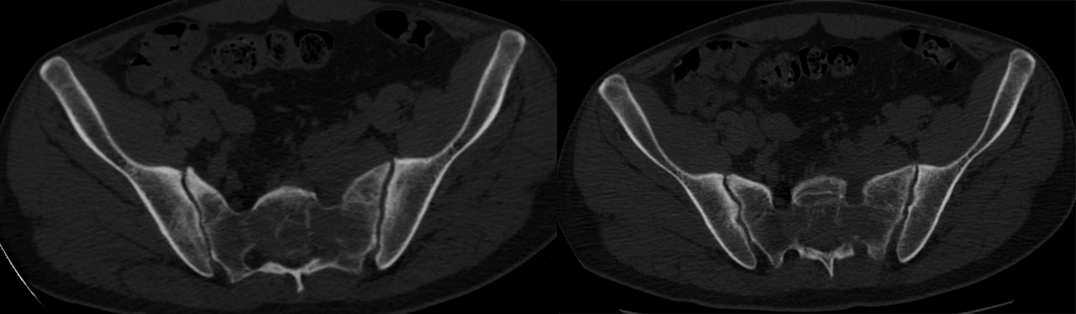

CT 平扫

PBL 的 CT 表现:骨质破坏、软组织肿块和骨膜反应。骨皮质破坏轻,一般不伴有骨质硬化,软组织肿块大是最典型征象。肿块呈等密度,轻中度均匀强化,少见坏死液化区;肿瘤有包绕椎体、附件、椎管生长趋势,易至椎管狭窄。 「云雾」征为骨小梁破坏吸收,稀疏、边界模糊不清,骨密度减低,原髓腔低密度区被软组织成分替代,致骨对比度降低,结构模糊不清,呈云雾状改变;「浮冰」征伴椎体压缩性骨折者,散在于软组织中的高密度残存骨形成「浮冰」样改变。